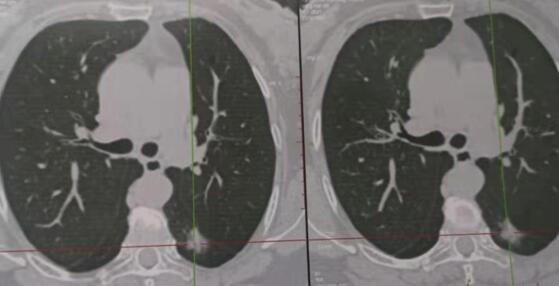

近日,腫瘤胸外科成功完成三例胸腔鏡下肺癌根治術(shù)。三名患者均系體檢時(shí)發(fā)現(xiàn)肺部直徑約15mm左右結(jié)節(jié),行多項(xiàng)檢查均考慮惡性不除外,但無(wú)法確診,來(lái)我科就診,根據(jù)患者病情,苗滿園主任帶領(lǐng)科室醫(yī)師經(jīng)研究討論,在全麻下行胸腔鏡下肺楔形切除送術(shù)中冰凍病理確診為肺癌,并行胸腔鏡下肺癌根治術(shù),手術(shù)順利完成,時(shí)間2小時(shí)??剖胰桃爰铀倏祻?fù)理念,少插管,早拔管,患者均快速、順利康復(fù)出院。該治療的成功引入,使我院腫瘤胸外科胸腔鏡手術(shù)水平躍上新臺(tái)階。